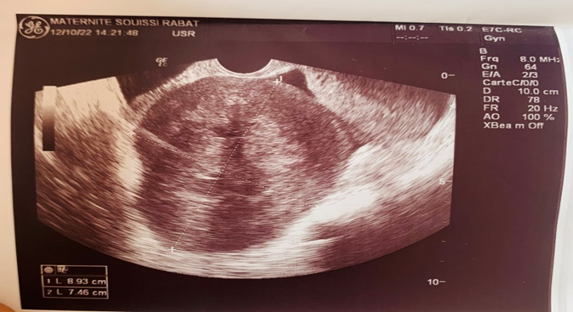

The clinical examination finds a Abdomin-pelvic mass lateralized on the left side, painless arriving halfway to the umbilicus. The abdominopelvic ultrasound combined with the transvaginal ultrasound objective the presence of a solid, movable, and non-homogenous echoic mass (7 × 8 cm) in the left side of the uterus most probably subserous uterine leiomyoma. No pathologic findings within the right ovary were found. Low effusion in the Douglas was detected. Pelvic MRI showed a large, well-limited mass with polylobed contours in the median and left latero-uterine area, in heterogeneous T1 and T2 hyposignal with discrete diffusion hypersignal, enhancing heterogeneously after injection of gadolinium. It measured 70×66×10 mm, a small pelvic effusion was associated.

Figure 1 Hypoechogenic latero uterine mass with echogenic zones of 7*8 cm.